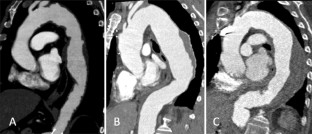

Fig. 2

Reprinted from Belvroy et al. published by PLOSONE, open access journals [11]

Fig. 3